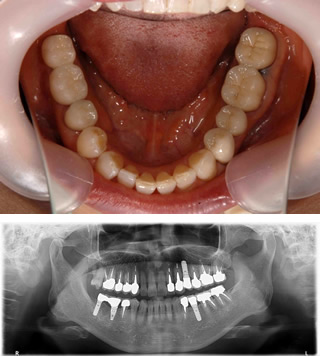

インプラント治療例

インプラント治療例1

• 1)平成24年10月9日 初診 62歳女性左下3本欠損

• 2)平成24年10月26日 インプラント3本埋入手術

3)平成25年2月19日 上部構造セット

• 4)治療後。現在もメンテ来院中。

インプラント治療例2

• 1)平成26年11月21日 初診 64歳女性

右下の歯(矢印の歯)他院で抜いたほうがいいと言われ相談に来院。過去に3本他院にてインプラント経験あり。当医院でCT撮影をしたところはっきり歯牙に破折が起きており抜歯が必要と判断しました。

• 2)患者様もCT画像を見て納得されて当院でのインプラントを希望されました。抜歯後、歯肉が治るのを待ってインプラントを埋入しました。

• 3)平成27年6月2日 右下 旧インプラントと連結して上部構造をセットました。